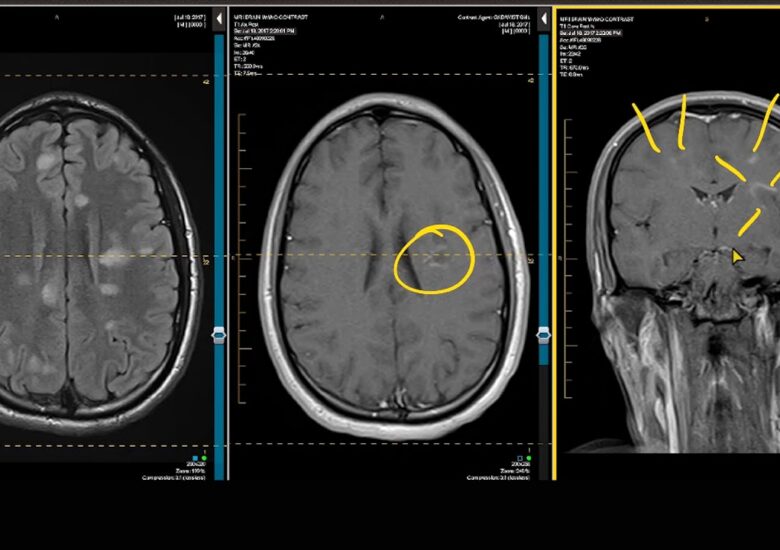

Spasticitatea este un simptom al sclerozei multiple (SM) care provoacă rigiditate musculară involuntară și spasme. SM apare atunci când sistemul imunitar al corpului atacă în mod eronat teaca de mielină,